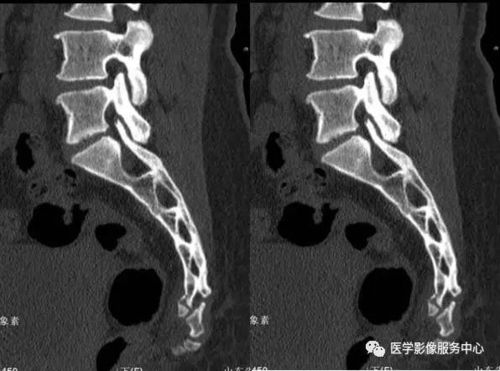

看图论病(尾椎骨折)

骶尾骨ct图片

尾椎骨ct